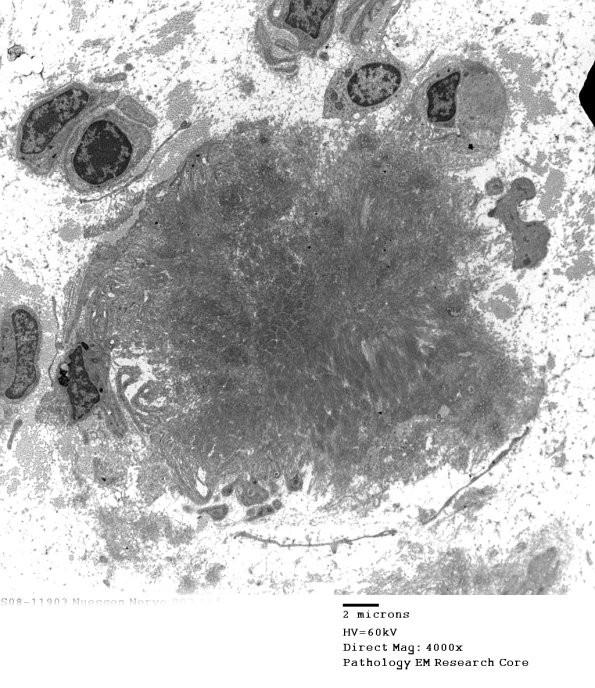

2F1-4 A discrete collection of amyloid is composed of filamentous aggregates. (electron micrographs)